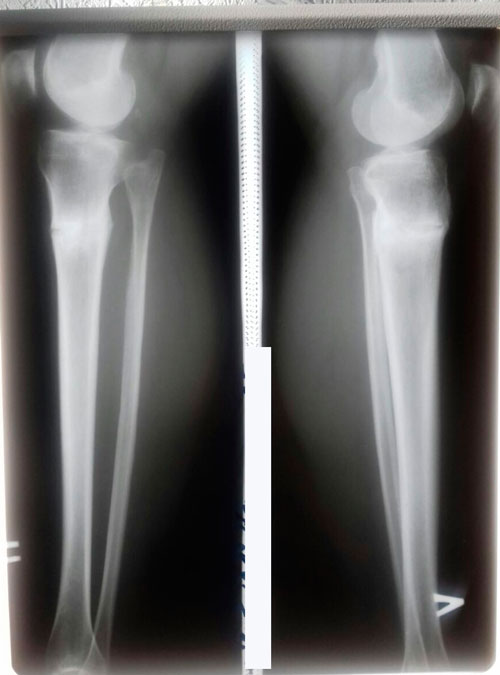

рентген и фото ножек, через 2 месяца с момента снятия аппаратов.

Сращение отличное, разрешено обувать каблучки, привыкайте к красивому!

Физические нагрузки разрешены (спорт) постепенно, по нарастающей.